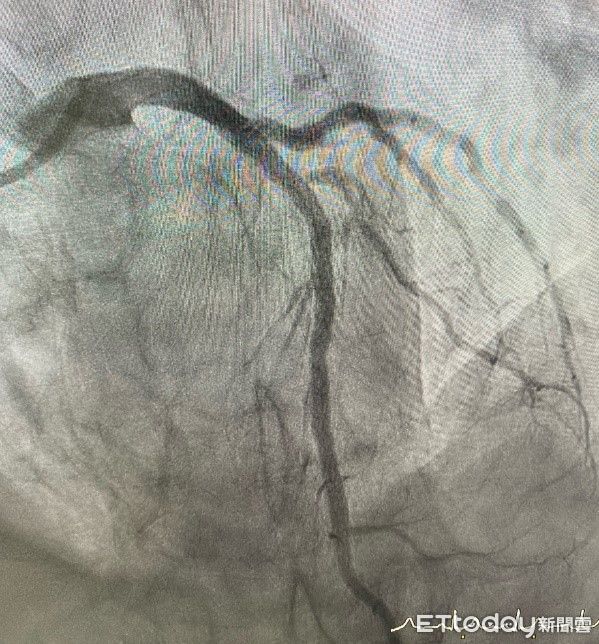

果然在心導管檢查後,顯示其冠狀動脈左前降支中段出現高達90%的嚴重狹窄,當日即施行血管擴張與支架置放手術,術後馬先生症狀明顯緩解,成功避免了可能發生的重大心血管事件。